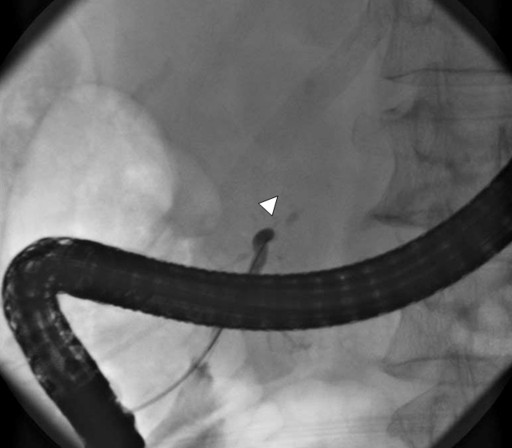

Seven years after clinical onset, abdominal CT revealed multiple pancreatic stones in an atrophic pancreas (Figure 2). ERCP (Figure 3) and magnetic resonance cholangiopancreatography (MRCP) (Figure 3) revealed stenosis of the main pancreatic duct in the head of the pancreas and upstream dilatation. MRCP (Figure 4) and ERC (Figure 5) revealed a longer stretch of stenosis in the hilar hepatic region. We tried steroid therapy in an attempt to ameliorate the stenosis of both the bile duct and the pancreatic duct, and prevent further progression. The initial dose of prednisolone was 30 mg, and this was gradually reduced. Two weeks, 7 weeks, and 11 weeks after the start of prednisolone administration, MRCP revealed no improvement of either the bile duct stenosis or the diffuse irregularity of the main pancreatic duct. The atrophic pancreas showed no change in size. The serum IgG and IgG4 levels decreased from 1,463 to 756 mg/dL (reference range: 870-1,700 mg/dL), and from 127 to 32.9 mg/dL, respectively. The steroid therapy was therefore stopped because of its ineffectiveness and the worsening of diabetes mellitus.

Figure 3. Endoscopic retrograde cholangiopancreatography showing obstruction of the main pancreatic duct in the head of the pancreas (arrowhead). |